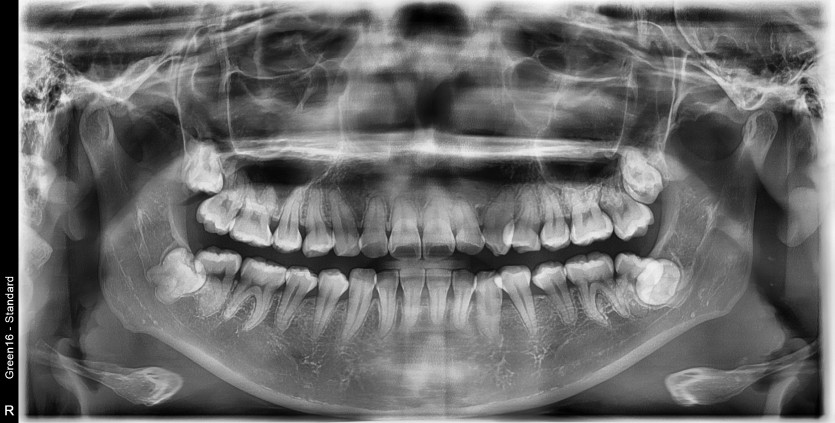

#28,38 사랑니 발치

구강외과 전문의가 당일 발치했습니다.